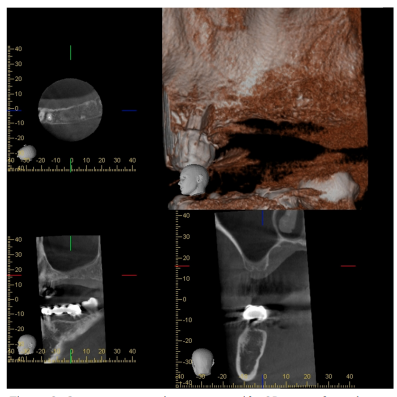

Tres meses más tarde, la paciente acudió de nuevo a la consulta con la finalidad de rehabilitar las ausencias de 25, 26 y 27, solicitándose un estudio mediante CBCT, en el que se observó una altura de1,63 mm y 11,6 mm de anchura (Figura 3).

Ante estos hallazgos se informó a la paciente sobre la posibilidad de rehabilitación con implantes, previa cirugía de elevación sinusal. Se solicitó de nuevo el consentimiento informado, y tras el mismo, se procedió a realizar la intervención bajo anestesia local con articaína al 4% y epinefrina 1:100.000 (Ultracain®).